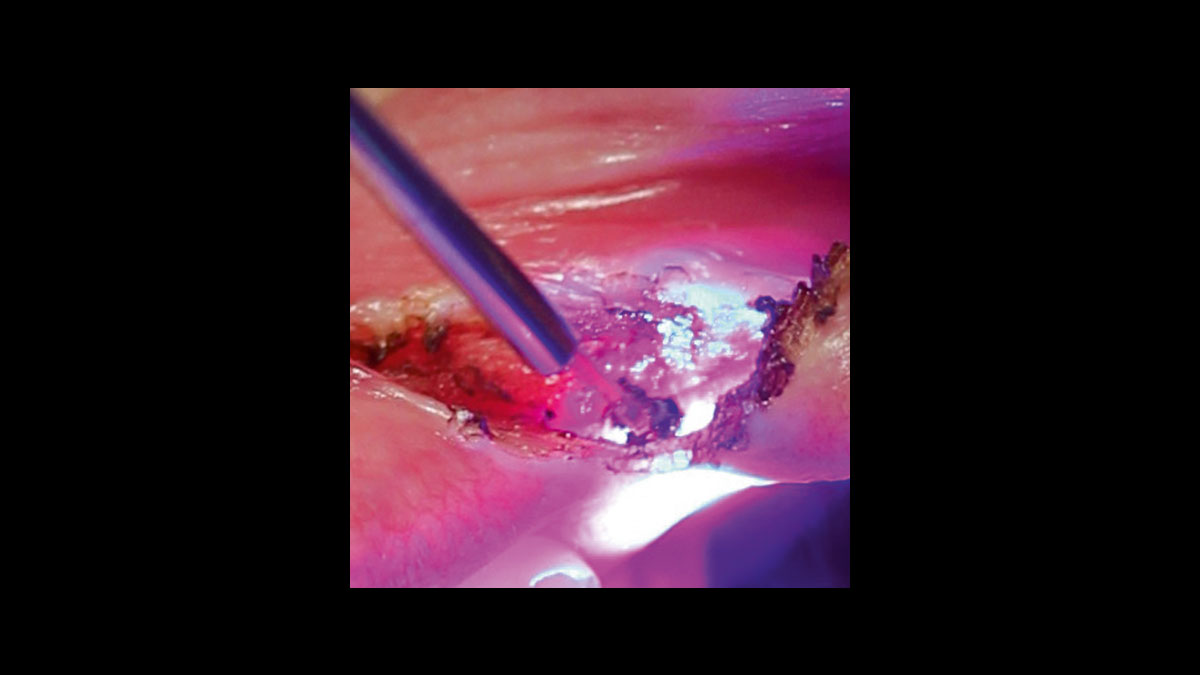

• Absceso

• Épulis

• Incisiones/escisiones